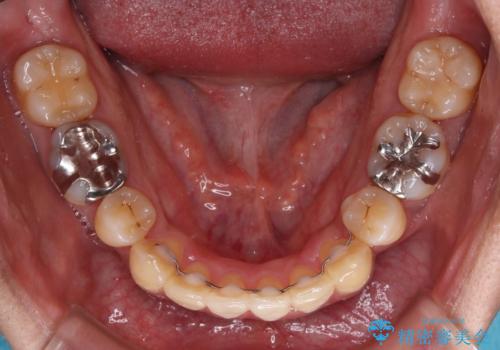

ワイヤー矯正と比較すると、八重歯が後方に傾斜した仕上がりとなりましたが、患者様ご希望のインビザラインにて十分な歯列を達成することができました。

- 1年8ヶ月

- 5-10回